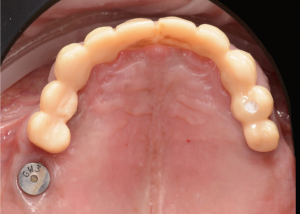

Second set of provisional restorations printed with GC Temp PRINT (medium shade) using the Asiga Max UV 3D printer. Fig. 13

Completed provisional crowns, implant retained crowns and bridge, characterized with OPTIGLAZE color (GC) – Dental technician: Brad Groblar, Oral Dynamics, New Zealand. Fig. 14

Completed provisionals fitted onto the printed models to allow the refinement of the contact points and occlusal contacts. Fig. 15 (i, ii)